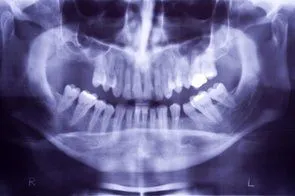

iStock_000002879017XSmall.jpg When you lose teeth, and do not replace them, the jawbone deteriorates where the tooth socket once was. This makes it difficult, and in some instances impossible to get dental implants or dentures later on. You may have not had the financial means at the time of the extraction for restorative surgery, but you may have the money now. The good news is that we can perform a process called ridge augmentation to restore the bone structure that is needed for restorative procedures such as dental implants. The process involves lifting the gum from the ridge to expose the defected area of the bone. Then the dentist uses a bone like substance to fill the defected areas. The ridge augmentation greatly improves the appearance of the mouth and increases the chances for success with the implants. With ridge augmentation, your implants will last for years.